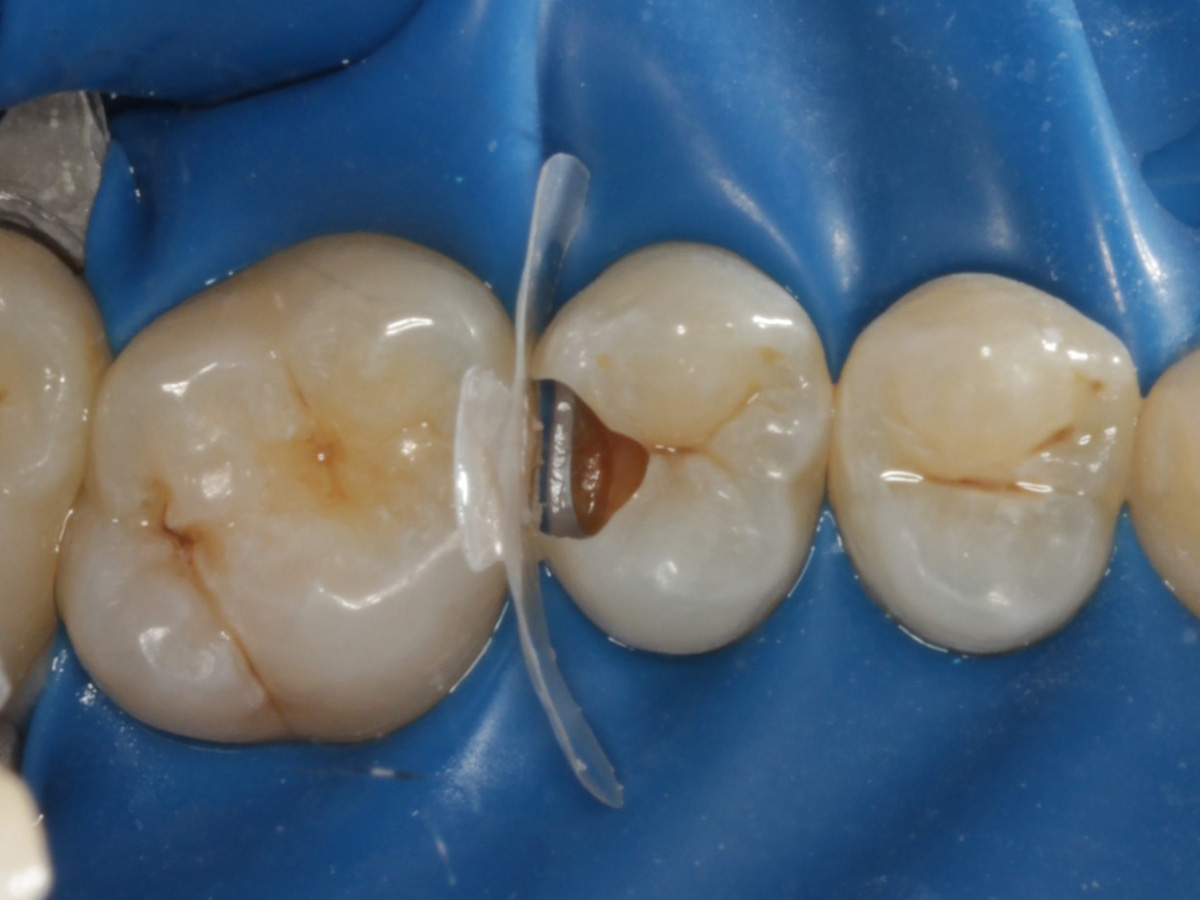

Abbildung 10

Nach Applikation der Matrize: Evolve Schwarz Prämolar- 7 mm; Schmelzätzung

Abbildung 11

Nach Spray und Trocknung der Kavität